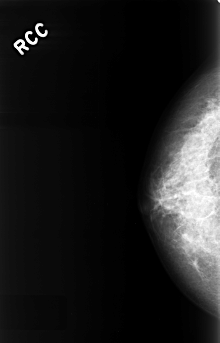

C_0323_1.RIGHT_CC

RIGHT_CC LINES 4448 PIXELS_PER_LINE 2848 BITS_PER_PIXEL 12 RESOLUTION 50 NON_OVERLAY